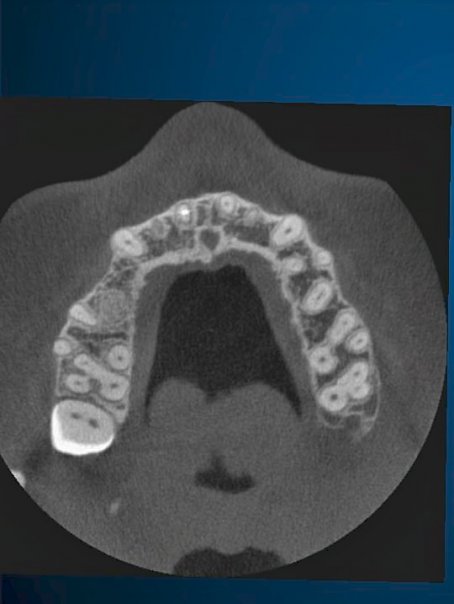

CT Scan Imaging

Computer Guided Implant Planning